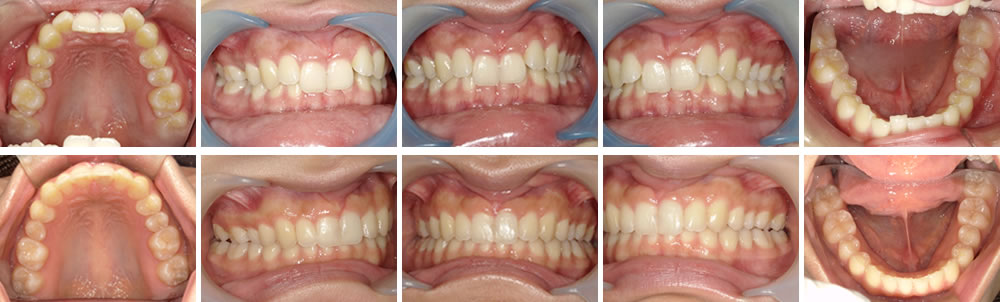

マウスピース矯正(インビザライン)で八重歯を改善した症例

年齢

30代

性別

女性

マウスピース矯正(インビザライン)で前歯のがたつきを改善した症例

20代

男性